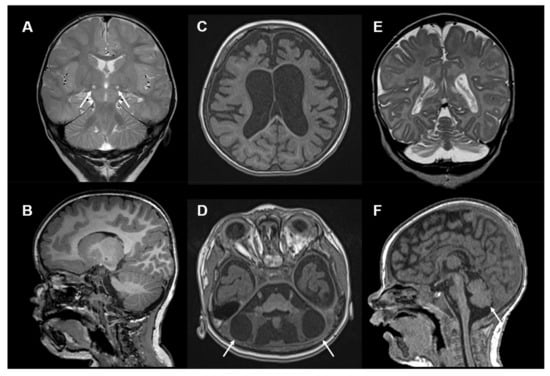

Examples of brain MRI imaging findings in COQ4 deficiency are depicted in Figure 3.

Figure 3.

Neuroimaging in COQ4 deficiency: (A) Brain MRI, T2-weighted, coronal images of a 15-month-old girl with COQ4 deficiency. Images show bilateral circumscribed lesions in the subthalamic nuclei (white arrows). (B) Sagittal T1-weithed MRI images show no cerebellar lesions. (C) Brain MRI, T1-weighted, axial images of an 18-month-old girl with COQ4 deficiency showing global brain atrophy. (D) Brain MRI, T1-weighted, axial images of the same child showing cerebellar degeneration with bilateral large cysts within the cerebellar hemispheres (white arrows). (E,F) T2-weighted, coronal and sagittal images and of a 2-month-old girl with COQ4 deficiency showing cerebellar hypoplasia (white arrow). Other MRI images of these individuals were published previously [30].